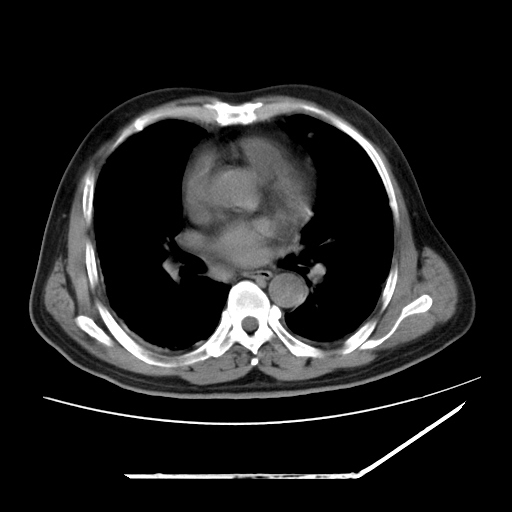

男,57,畏寒,发热

两肺野多发大小不一高密度灶,纵膈内见肿大淋巴结,要考虑转移瘤可能。双侧胸腔少量积液。

双肺多发结节样病灶,部分内见透光区,纵隔内见淋巴结肿大。结核临床如有畏寒,高热,白细胞增高首先考虑迁徙性肺脓肿(多是金黄色葡萄球菌感染)。

注意除外转移瘤。

1)考虑两肺感染性病变(金黄色葡萄球菌肺炎?);建议抗炎治疗后复查排除其他。2)双侧少量胸腔积液。